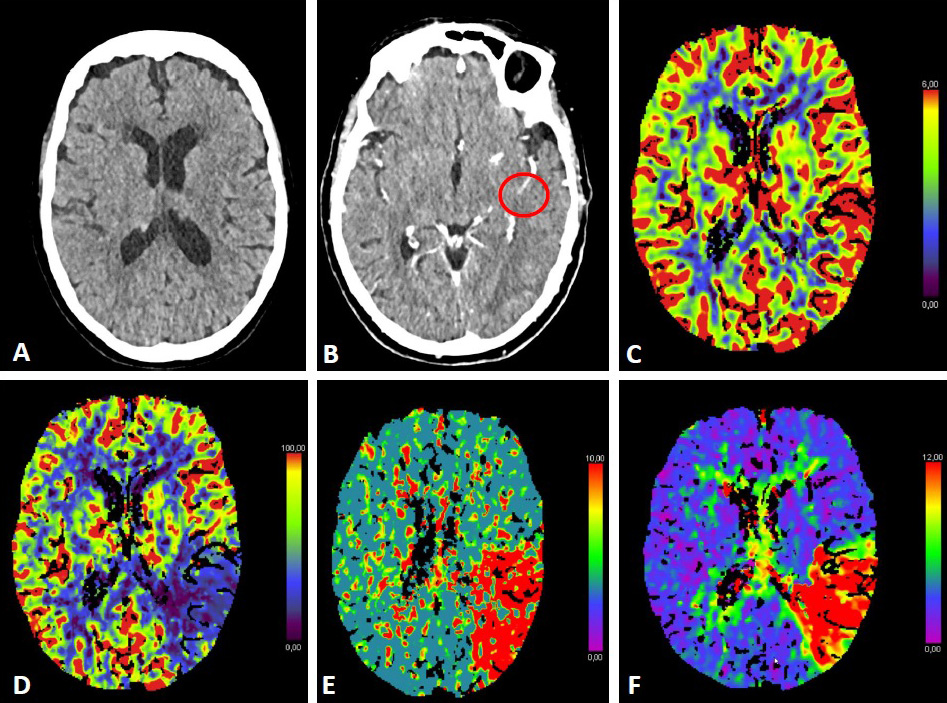

Fig. 1.ASPECTS. Visualization of the ASPECTS territories (A,B). The following areas are covered: M1 (anterior MCA cortex, frontal operculum), M2 (anterior temporal lobe, laterally to the insula), M3 (posterior temporal lobe, posterior MCA cortex), M4 (anterior MCA cortex superior to M1), M5 (lateral MCA cortex superior to M2), M6 (posterior MCA cortex superior to M3), insula (I), internal capsule (IC), caudate (C), and lentiforme nucleus (L). Each area accounts for 1 point. The maximum ASPECTS score is 10. Hypodensity in a described area leads to a deduction of one point. (C,D) show an example of CT ASPECTS. Hypodensity in the M2 and M6 areas is observed. Total ASPECTS: 8.